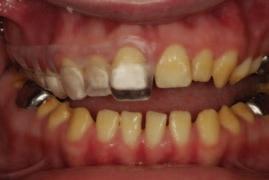

FIGURE 1: Orthopantogram post endodontic treatment demonstrating the extension of the root canal material (AH Plus) along the inferior alveolar canal.

Radiographic examinations consisted of digital orthopantomogram (OPG), peri-apical (PA), and cone beam computed tomography (CBCT) scans. The scans revealed that the lower left first molar root canals were obturated with a radiopaque material, and showed root canal filling extending beyond the apices of the tooth and approximately 5cm along the mandibular canal ( Figures 1 , 2 and 3 ).